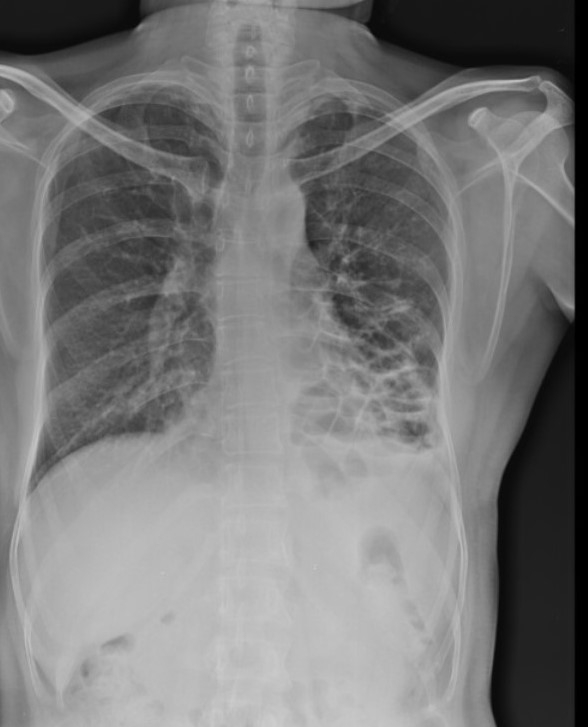

Diagnosis?

Large left pneumothorax